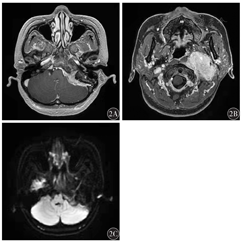

影像学检查:CT检查示左侧后颅窝骨质密度增高,内板呈毛刷状改变,累及左侧颞骨乳突部及岩部、枕骨大孔及斜坡。左侧后颅窝底、邻近颈静脉孔区及左侧咽旁间隙颈动脉鞘可见明显强化肿块影,其内可见钙化,肿物自后颅窝经颈静脉孔向颈部蔓延,左侧颈内动脉颈段被包绕其中并向外前方移位,邻近颈内静脉显示不清,左侧颈静脉孔增宽,左侧内听道变窄,左侧鼻咽、口咽腔变窄,左侧茎突受压推挤向前外侧移位。左侧鼓膜稍增厚,鼓室内软组织密度影(图1)。增强磁共振成像(MRI)示左侧咽旁间隙及颈动脉间隙可见团块状明显强化影,信号均匀,边界尚清,大小约6.0 cm×5.2 cm×3.6 cm,病变包绕左侧颈内动脉颅外段、颈内静脉,并沿左侧颈静脉孔、左侧舌下神经管与颅内左侧桥小脑角池区同类病变相延续,相应颅底孔道略扩大并充满强化影,左侧面听神经被包绕,邻近硬膜轻度增厚强化并延续至椎管内。病变周围左侧颞骨、枕骨增生硬化,局部见膨胀性骨质压迫吸收,左侧茎突受压移位。病变周围左侧腮腺及左侧颈后肌群前外侧缘受压改变,左侧头长肌、咽黏膜间隙受压前移,咽鼓管显示不清,脑实质未见明显异常强化(图2)。综合影像学结果后诊断为沟通性MEP。